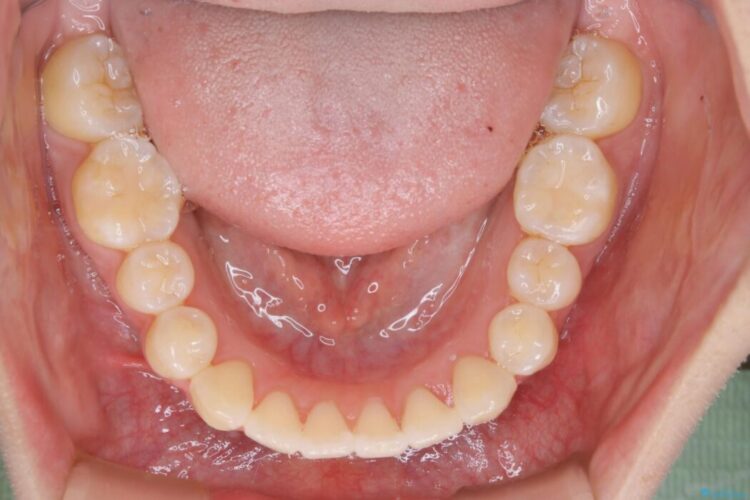

特に前歯部分に90度近く捻転した歯、斜めに生えている歯などによる歯列のがたつき、正中のズレが目立っていました。

奥歯から遠心移動とディスティング(歯の側面を僅かに削る)を行うことで歯列を整えるスペースを確保し、患者様のご要望からインビザライン装置での矯正を計画しました。

本症例では奥歯から順に移動させるため前歯の変化を感じるには時間が掛かりましたが、インビザライン装置とマイクロインプラントを併用することで健康な歯を抜歯することなく歯列をきれいに整えることができました。